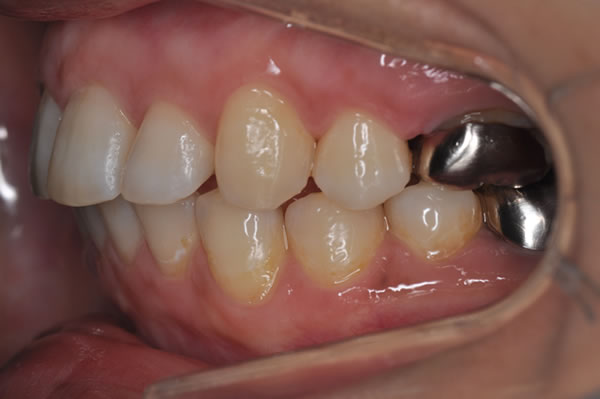

上顎前突症の治療例

上顎前突症(出っ歯)の矯正症例 ケース01

| 治療前(初診) | 治療後 | |